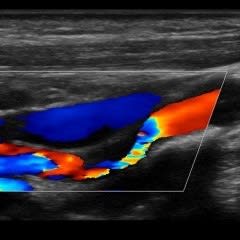

Vascular Services

Allow our dedicated team to put you at ease, while we boast about having top of the range equipment and overqualified staff. Outstanding patient care comes as standard here at NumiScan Basingstoke.